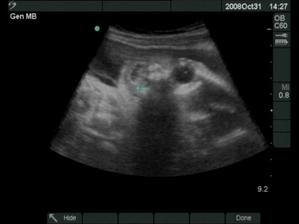

18.12.2008 prišli na svet o 3 týždne skôr naše krásne dvojičky. Ako prvá predrala cestu svojmu bratčekovi Laura, ktorá išla hlavičkou. Prišla na svet 12:53 a vážila 2720 g a merala 46 cm. Marko mal výjsť hneď na to zadočkom, ale keď zistil že sa mu uvoľnilo miesto asi si to rozmyslel a rozhodol sa v brušku zostať a spriečil sa. Pán doktor ho musel síce trochu povykrúcať aby ho dostal von, ale našťastie sa mu to podarilo a nemuseli maminu po normálnom pôrode aj rezať 🙂 Svetlo sveta uzrel Marko 13:03 a vážil 2890 g a meral 48 cm.